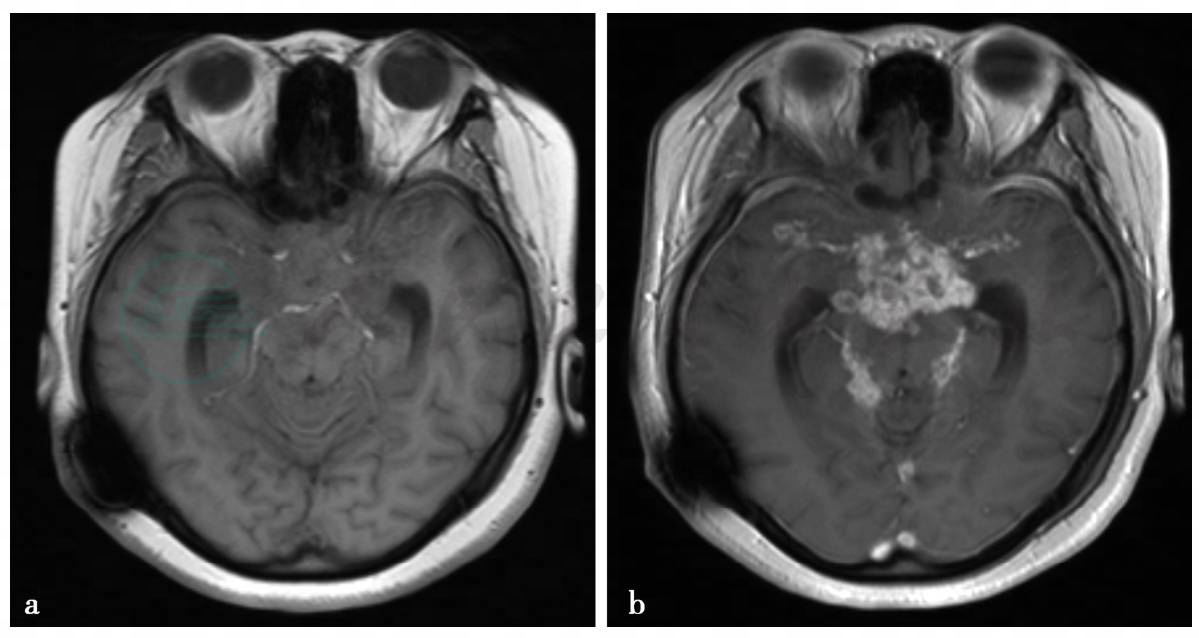

(1)病例6,女性,14岁。头疼、恶心、呕吐8个月余伴双下肢无力,病情加重1个月余。脑脊液:黄色、浑浊,白细胞计数530×106/L,蛋白定量6720mg/L,氯化物101.2mmol/L,葡萄糖3.88mmol/L。胸部正位片:双肺结核。

(1)病例6:

MRI平扫及增强扫描。

图1 a,T1WI见鞍上池、环池闭塞,正常低信号脑脊液影消失,成等信号影。b,T1WI增强扫描见鞍上池、环状内多发环状、小结节状、条片状强化

(1)病例6,结核性脑膜炎。